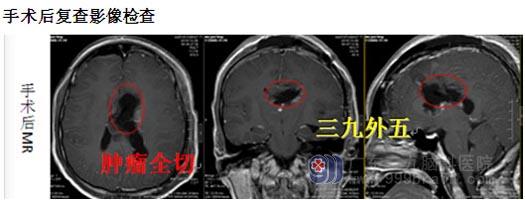

近日,一名17岁的少女在广东三九脑科医院综合神经外科完成巨大中枢神经细胞瘤切除手术,肿瘤一次性全部切除,功能区保护完好。目前,患者恢复良好,即将康复出院。

一周的放疗结束后,综合神经外科鲁明主任主刀在全麻下行“左侧侧脑室巨大肿瘤切除+脑室外引流+硬脑膜修补术”,取左侧经额中回入路,术中见肿瘤呈灰白色,质软,血供丰富,显微镜下将肿瘤分块全部切除。术后病理提示:不典型中枢神经细胞瘤,WHO II级。